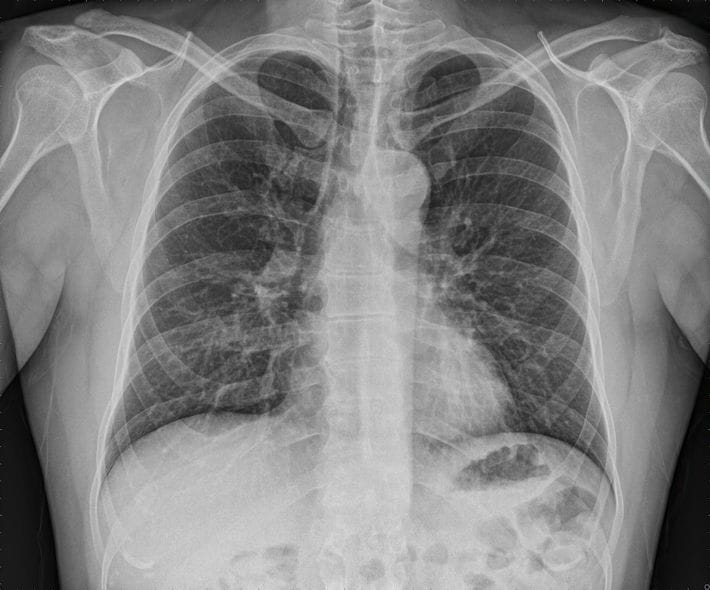

長嶋茂雄さん訃報から見直す「肺炎予防」…血液サラサラだけではない週2摂取で肺強化が期待できる身近な食材

※写真はイメージです